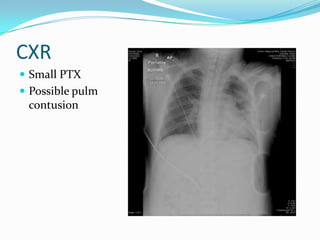

CXR

 Small PTX

 Possible pulm

contusion

CXR  Small PTX Possible pulm contusion